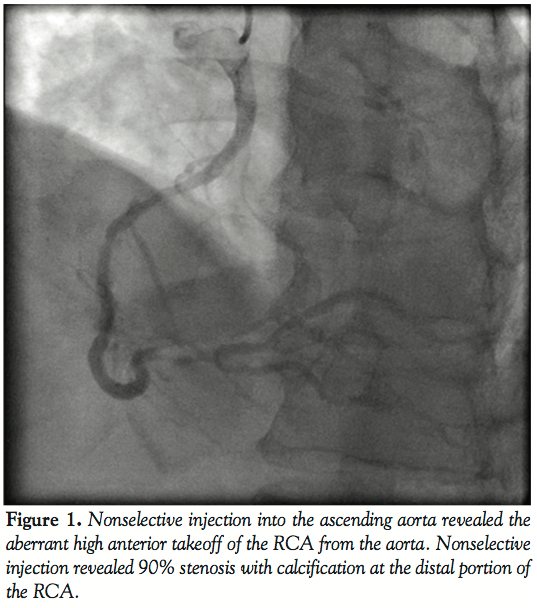

Selective cannulation of the RCA could not be achieved with Judkin’s right 4.0 catheter. Nonselective injection into the ascending aorta revealed the aberrant high anterior takeoff of the RCA from the aorta. Nonselective injection revealed 90% stenosis with calcification at the distal portion of the RCA. Following angiography, we performed PCI of the mid LAD.

The post-procedural recovery of the patient was uneventful and thus he was discharged from the hospital with double anti-platelet therapy (100 mg of aspirin and 75 mg of clopidogrel sulfate) on the following day. One month later, the patient was re-admitted for PCI because of persistent chest pain on effort despite medical treatment. He was diagnosed 90% stenosis with severe calcification at the distal portion of the RCA by computed tomography. On the other hand, there was no stent thrombosis at the implanted stent lesion of LAD. We performed PCI of the RCA under local anesthesia and a 6 Fr sheath introducer was inserted into the right brachial artery. We inserted a 4 Fr multipurpose angiographic catheter into a DIO thrombus aspiration catheter to deliver it to the ascending aorta. The DIO was functionally stabilized to find the RCA ostium by manipulating the angiographic catheter. When the angiographic catheter successfully engaged the RCA ostium, we glided the DIO catheter forward and pulled out the angiographic catheter to perform angiography. RCA injection clearly revealed 90% stenosis with calcification. The lesion was crossed with a Neo’s Fielder guidewire (Asahi Intech Corporation), and pre-dilated with a 2.0 mm × 15 mm Lacrosse balloon catheter (Goodman Co. Ltd., Aichi) at 10 atm. We tried to deliver an Eagle eye IVUS catheter (Volcano Corporation), but it did not cross the lesion because of insufficient back-up force.